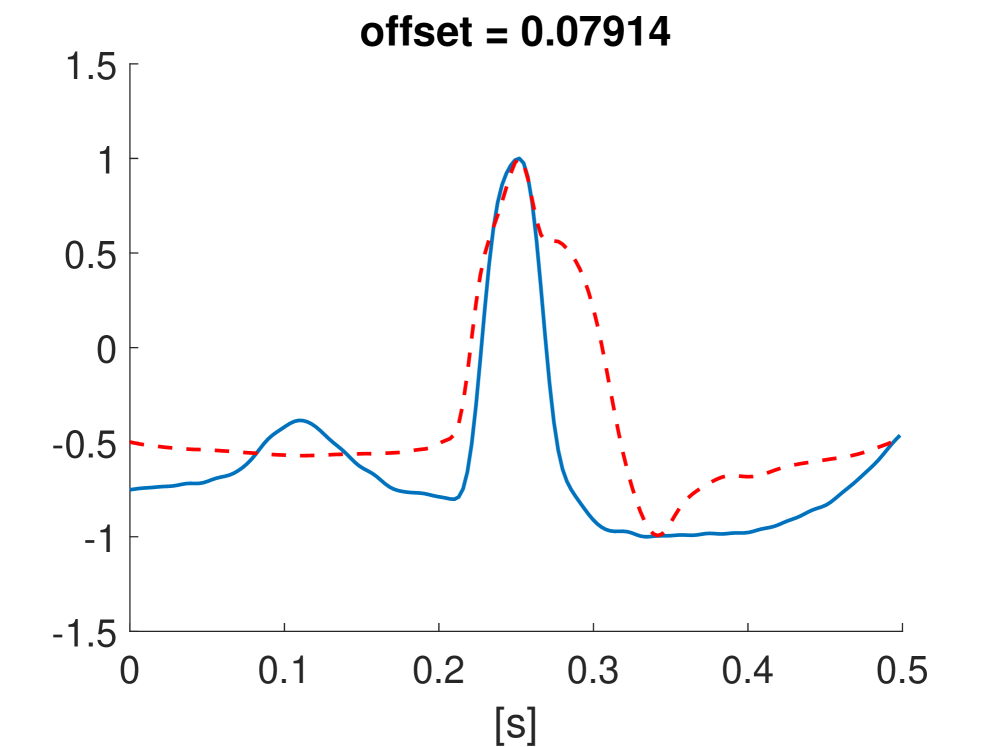

Fig. 10 shows the result in input space of moving along the first principal components in the latent feature space. As original base point we take a normal beat signal, i.e. corresponding to a hidden unit on the bottom right of Fig. 9(a). The smooth transition between the beat patterns allows for interpretation of the first principal components. This allows a clinical expert to understand on what basis the paced beats are separated by the principal components and if this basis has a physiological meaning. In order to investigate the separated region of the latent space at the top of Fig. 9(b) we start from a paced beat pattern and vary along the third principal component. This allows us to see which sort of heartbeat patterns are responsible for this specific distribution in the latent space.